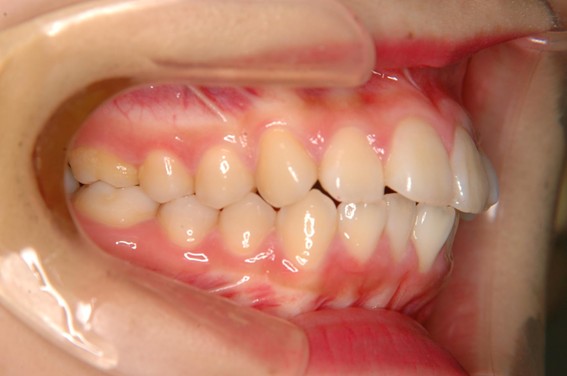

| 主訴 | 前歯が逆に噛んでいる。 |

| 治療内容 | 表側ワイヤー矯正、ジルコニア補綴を行いました。 |

| 治療費 | ワイヤー矯正660,000円(税込) ジルコニア176,000円(88,000円×2歯)(税込) |

| 治療期間 | 30ヶ月 |

| 治療回数 | 30回 |

| 想定されたリスク | 歯根吸収、歯髄壊死、歯髄充血、歯肉退縮のリスクがありました。 |

骨格性Ⅲ級・前歯部反対咬合の症例でした。反対咬合のまま治療していた前歯のサイズ不調和を、表側ワイヤー矯正とプロビジョナルクラウンで調整。正中を整え、犬歯・臼歯ともⅠ級、適切なオーバージェット(上下前歯の前後的な距離)・オーバーバイト(上下前歯の垂直的な重なり)に仕上げました。